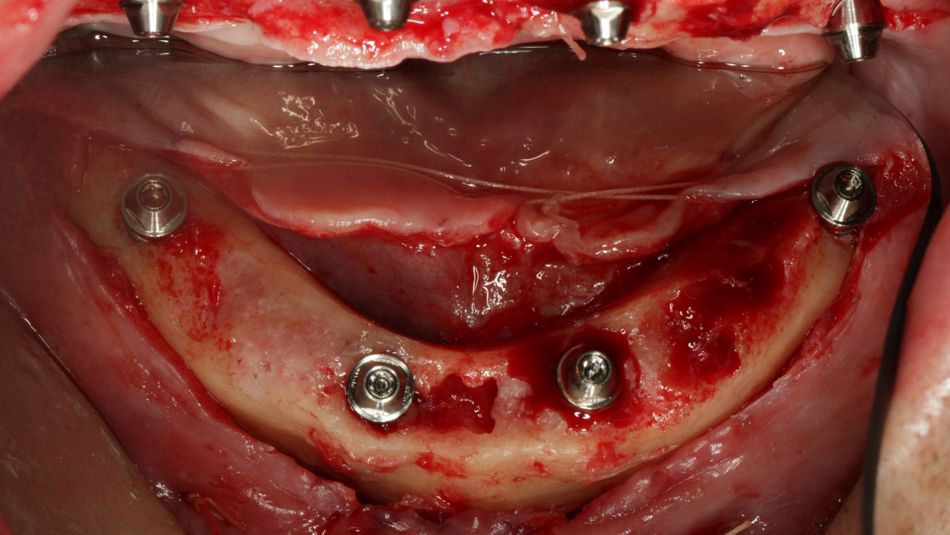

Treatment: The treatment plan was performed with a computer software and included the use of four straight Straumann® BLT implants in the lower jaw. Following local anesthesia, and a mid-crestal incision was done. The flap was raised with minimal trauma, the inflamed tissue was removed, and the bone level was adjusted. The implant bed was prepared with the help of a guide and the manufacturer’s protocol was followed. Two implants were placed behind the mental foramina and two in front of it, providing an ideal spread. The placement of implants in resorbed bone led to the need of bone augmentation around the exposed surfaces of the implant. After the surgical procedures, the bite registration was performed, and the impression was sent to the laboratory. Couple of hours later, the temporary prosthesis was placed on the patient and the occlusion was checked.